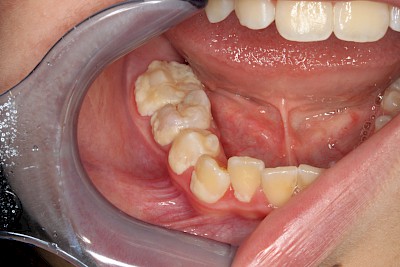

Lagern sich Mineralien wie Calcium und Phosphat aus dem Speichel in den Zahnbelag ein, so bildet sich oberhalb vom Zahnfleisch gelb-beiger harter Zahnstein. Zahnstein kann nicht mit der Zahnbürste weggeputzt werden und erschwert die Mundhygiene zusätzlich.

Vor allem dort, wo große Speicheldrüsen den Speichel in die Mundhöhle entlassen, bildet sich besonders schnell Zahnstein:

- An den Außenflächen der Oberkiefer-Molaren (Backenzähnen)

- An den Innenflächen der Unterkiefer-Frontzähne